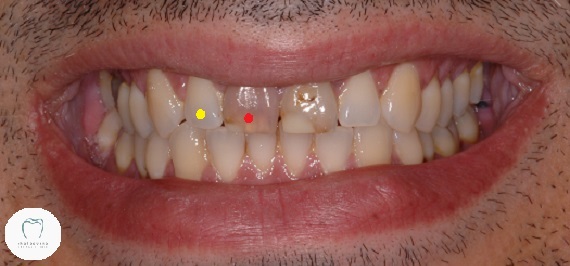

I completed this really interesting dental crown case last week. (Well, I hope I’ve completed it. More on that later!) This gentleman presented last year in pain and with two dark teeth at the front that looked like this:

Both teeth are badly discoloured and heavily filled. His upper right central (red dot) tooth was hurting. A lot. If we tapped on it, there was even more pain. So we took an X-ray and found this: